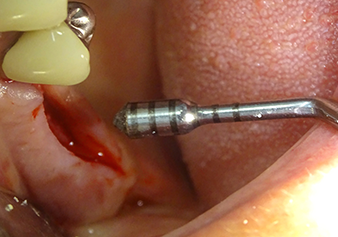

Implant bed preparation and augmentation

Following an intermediate check (Fig. 4) a further preparation step was performed (Fig. 5). Afterwards, the hydraulic Z35P instrument was used to lift the membrane to the desired position (Fig. 6 and 7). This was followed by further piezosurgical preparation of the implant bed, concluded with a rotary bur and shoulder milling cutter up to the implant diameter of 4.8 mm. Before the implant was inserted, the augmentation material (particle size approx. 0.8-1.6 mm) was introduced underneath the Schneiderian membrane (Fig. 8).